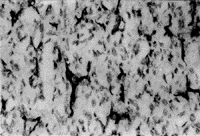

FⅧ-RA和CD31阳性产物定位于血管内皮细胞浆(图1),80例骨肉瘤中50例两种抗原皆为阳性,另外30例中FⅧRA阳性16例,CD31阳性14例。因此,本组肿瘤微血管密度是综合FⅧRA和/或CD31免疫组化染色结果计数的。80例骨肉瘤中MVD值范围为7.3~93,中位数为31.1,平均值为35.4。

图1 骨肉瘤CD31免疫组化染色,显示肿瘤

微血管密度,LSAB×200